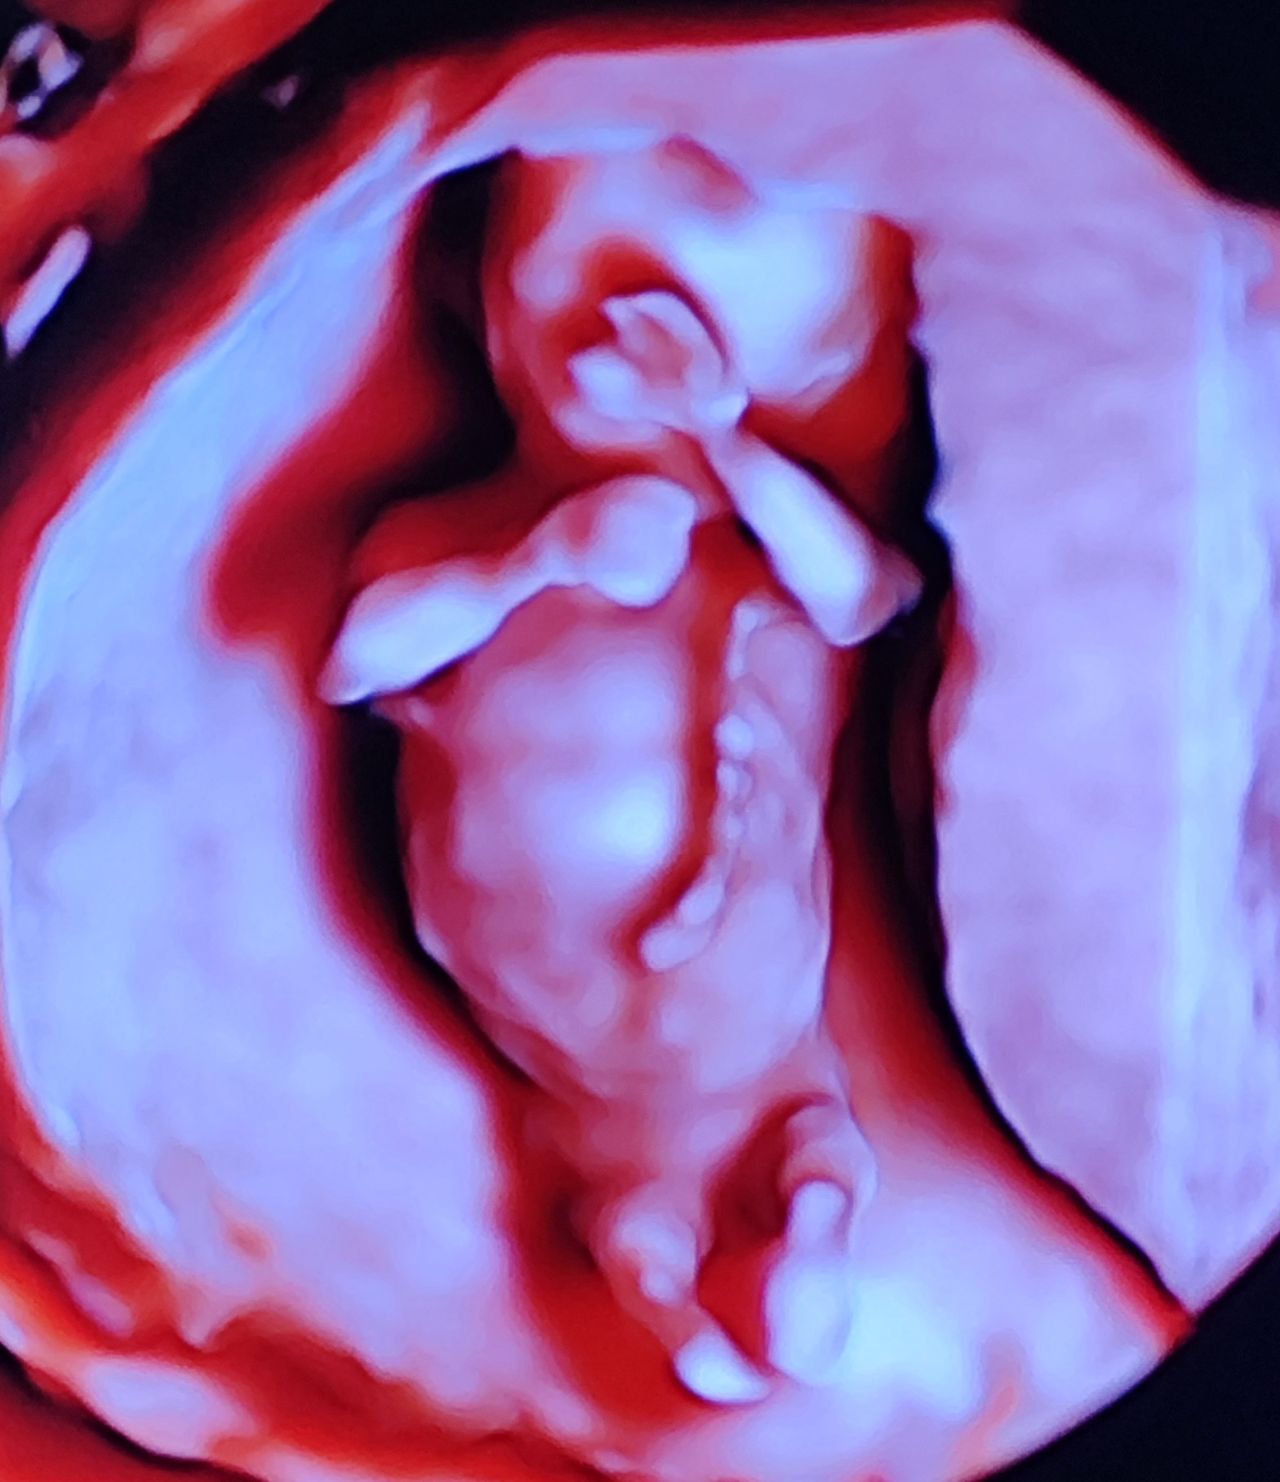

Dal 2015 al 2016 , frequenza presso U.O. Santa Maria delle Croci , Ravenna , periodo di Training di Chirurgia Laparoscopica, Endoscopica e di Isteroscopia ambulatoriale /office. In quell'anno nella stessa sede , ho  frequentato L'Ambulatorio di Diagnosi Prenatale acquisendo competenze in Ecografia Ostetrica del I-II-III trimestre.  Dopo la specializzazione ho proseguito la formazione e l'aggiornamento in particolare occupandomi dell’ Ecografia in ambito Ostetrico.

Ho acquisito "Certificate of Competence " da parte della Fetal Medicine Foundation per l'ecografia dell'11-13 settimana di gravidanza .

Da Maggio 2017 ad oggi faccio parte dello STAFF dell’Unità Operativa di Ostetricia e Ginecologia presso l’Ospedale "degli Infermi" di Faenza e dell’Ospedale "Morgagni Pierantoni "di Forli e mi occupo principalmente di Ostetricia , Gravidanza a Rischio, e dell'Ambulatorio Diagnosi Prenatale dove eseguo ecografie genetiche del I trimestre ed ecografie morfologiche e del III trimestre di gravidanza .